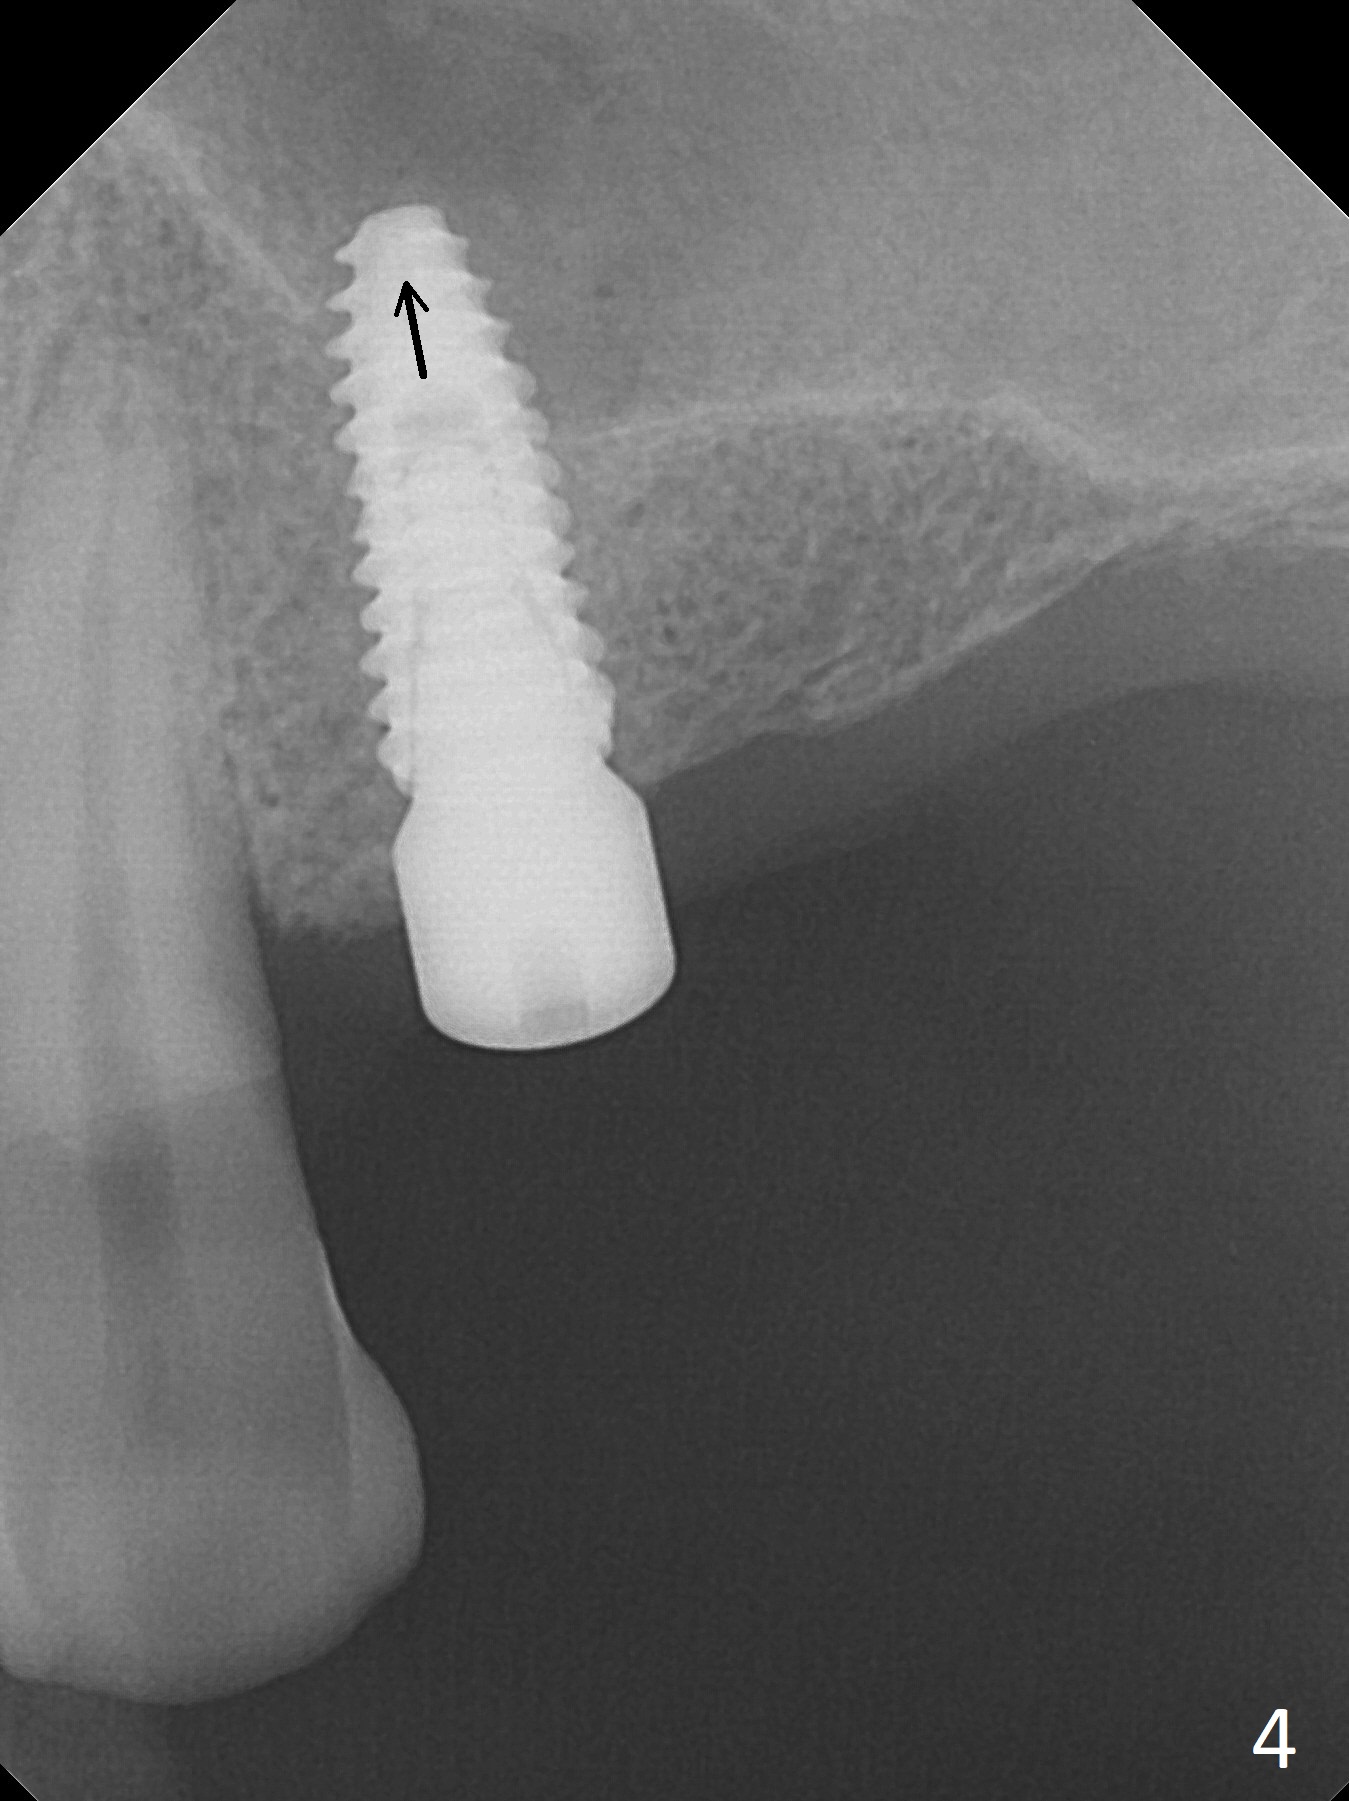

After a 4x10 mm implant is placed with fixture mounting (Fig.2 M) following sinus lift (*) at #12, osteotomy is initiated at #10 (Fig.1 (T: tube of surgical guide)). It appears that the drill (D) has good trajectory (between the Incisive Canal (red dashed line) and the canine root). The final position of the implant at #10 is acceptable (Fig.3). The implant at #12 is placed deeper (Fig.4 (arrow), as compared to Fig.2) because of clinically buccal superficial placement. The most critical challenge is anterior deep bite associated with posterior collapse. Periodontal dressing is applied. When the latter dislodges, there is minimal clearance for a provisional. Periodontal dressing is re-applied. The patient (smoker, partial edentulism with occlusal interference) returns for provisional nearly 1 month postop with chief complaint "something is lost in the back". In fact the healing abutment at #12 is lost with buccal granulation tissue (Fig.5). When a new abutment is seated, there is discomfort. When a healing screw is placed, it cannot be seated completely with two separate trials (Fig.6,7). Should we leave it as it is or open up for complete seating? It appears that the implant is loose. After preparation for clearance at #10, the abutment is retightened. It appears to turn with the underlying implant with discomfort. A 4x5 mm healing abutment is placed to reduce micro-movement. One week later, the infection at #12 dissolves with oral Amoxicillin (Fig.8). Due to limited occlusal clearance and implant tenderness when the abutment abutment is retightened, the cemented abutment is changed to a healing abutment. The implant at #10 seems to be osteointegrated, while the healing screw at #12 remains incomplete seating 3 months postop (Fig.9). The loose healing screw cannot be retightened securely, as there is bone loss around the implant 3 months postop (Fig.10 *). When a 4.5 mm x 15 degree 4 mm cuff angled abutment is placed, the mesiodistal trajectory improves (Fig.11), but there is no occlusal clearance (Fig.12). The latter would form when posterior support is established (Fig.13, either removable appliance (which the patient hates) or fixed one (finance)). Fig.14 shows the unhealed site of #12. Incision confirms the bone loss around the implant, which is removed. Although the sinus floor is absent, there is no membrane perforation. After debridement, allograft mixed with small amount of Osteogen is placed (Fig.15,16 G) and covered with Osteogen plug and 6-month membrane.